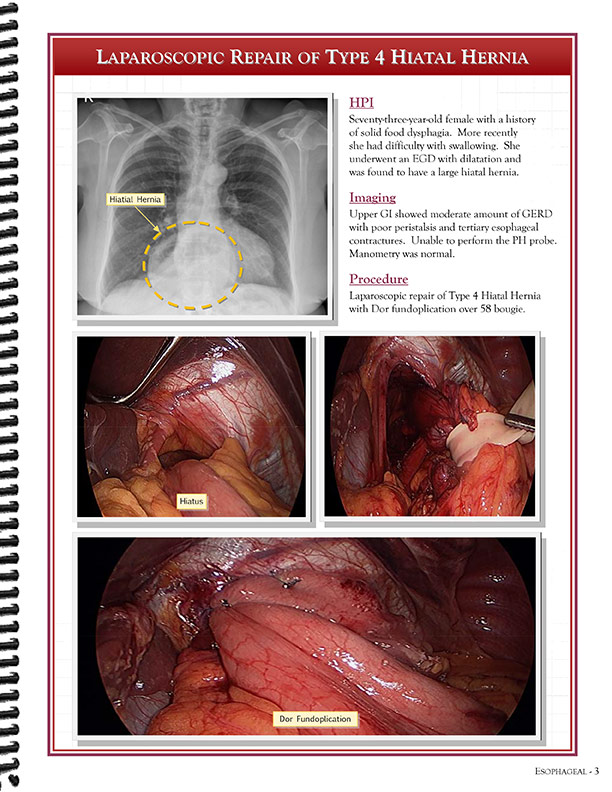

Cardiothoracic Surgeons' Case Studies Referral Booklet